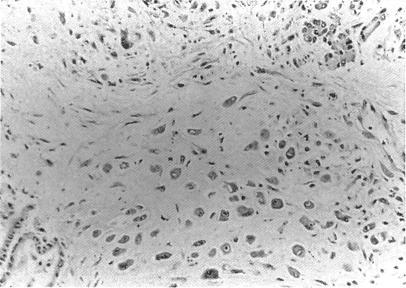

Disseminated cytomegalovirus infection.

Genitourin Med. 1992 Apr;68(2):75-9. doi: 10.1136/sti.68.2.75.